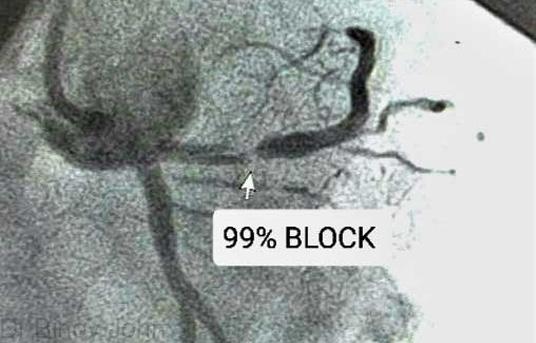

He has proven skill and experience in performing the most complex of complex angioplasties like rotablation angioplasty of calcified blocks, by-pass graft angioplasty, chronic total occlusion, left-main and bifurcation angioplasty.

COMPLEX CORONARY ANGIOPLASTIES

ROTABLATION ANGIOPLASTY: Angioplasty of calcified (stone-like) blocks | BY-PASS GRAFT ANGIOPLASTY: Angioplasty of blocks in by-pass grafts after By-pass surgery | CHRONIC TOTAL OCCLUSION (CTO) ANGIOPLASTY: Angioplasty of 100% blocks | LEFT MAIN ANGIOPLASTY BIFURCATION ANGIOPLASTY|MULTI-VESSEL ANGIOPLASTY: Angioplasty in 2 or 3 arteries | PRIMARY ANGIOPLASTY: Angioplasty in heart attack patients.